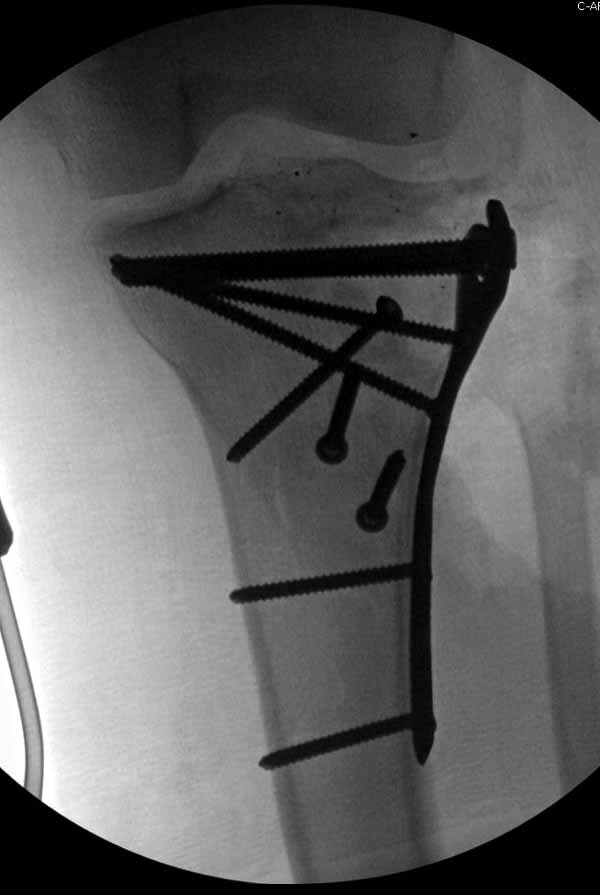

----------- следущая часть -----------

Вложение не в текстовом формате было извлечено…

Имя     : 26 Flexur molding.jpg

Тип     : image/jpg

Размер  : 48617 байтов

Описание: отсутствует

Url     : http://weborto.net:8080/pipermail/ortho/attachments/20110617/500d7d65/attachment-0010.jpg